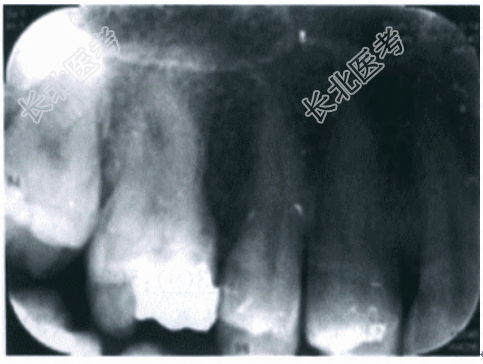

病历资料1.主诉 右上后牙疼痛1周,加重2天。2.现病史:患者,女,41岁。患者右上后牙充填体数年,无不适感,1周前咀嚼食物时疼痛不适,能明确指出患牙,近2天疼痛渐加重,疼痛为持续性、自发性、局限性,无冷热刺激痛,右上后牙不敢触碰,来我科就诊。否认咀嚼硬物。3.既往史:否认系统性疾病史、传染病史;否认药物过敏史;无烟酒嗜好。4.临床检查:(1)体格检查:神清,对答切题,痛苦面容。R19次/min,P79次/min,BP142mmHg/85mmHg,T38.1℃;双侧面部对称,皮肤无红肿,右侧上颌窦区无压痛,右侧下颌下淋巴结、颏下淋巴结肿大,有触痛。(2)专科检查:口腔卫生可,16牙近中邻

面可见大块牙色充填体,探诊充填体边缘密合,牙齿无探痛,垂直叩诊(+++),侧向叩诊(+),扪诊根尖部(+),无波动感,松动Ⅰ度,冷诊无反应,电活力测试无反应;牙龈略红肿,触诊不痛;根尖部颊黏膜红肿;余牙检查无特殊情况。5.辅助检查 X线片检查示:16冠部充填物影像,牙周膜间隙增宽,髓室及近中颊根管影像不清,根尖未见明显异常(见图10-1)。